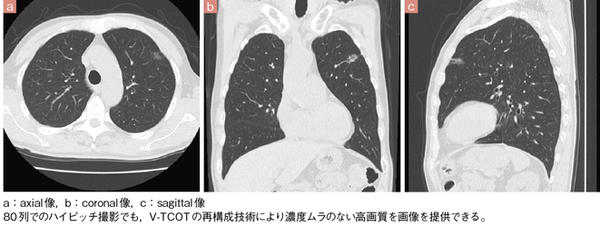

■症例2 胸腹部(ハイピッチ撮影)

再構成技術であるV-TCOTや,高い空間分解能を実現するダブルスライステクノロジーにより,Aquilion PRIMEでは画質の点でも,これまでのマルチスライスCTから進化している。三田助教は,V-TCOTの効果について,従来の装置と比較し,画質の均一性が増してアーチファクトが減ったことを評価しており,「腹部領域ならば,肝臓や肋骨の下,裏側のノイズとアーチファクトが解消されています」と説明する。

Aquilion PRIMEの画質については,井田係長も64列に比べ格段に向上したと評価している。「Aquilion PRIMEでは,長年マルチスライスCTを開発してきた東芝社の技術が熟成されたように思います。アーチファクトの減少や,view数が増えたことによって中心部と周辺部の画質の差がなくなり,均一性が良くなりました。例えば,整形領域での肩の撮影など,寝台の中心に位置決めできない症例でも,高画質画像を得ることができます」と述べている。